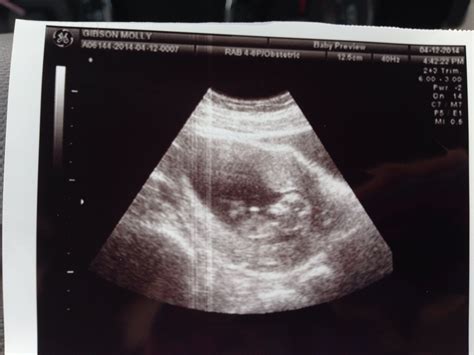

11 Week Ultrasound Pictures

Pregnancy is an exciting journey filled with milestones, and one of the most anticipated moments is the 11-week ultrasound. This scan provides valuable insights into the baby's development and offers parents their first detailed glimpse of their growing child. Understanding what to expect from 11 week ultrasound pictures can help alleviate anxiety and build excitement for this significant event.

Interpreting 11 Week Ultrasound Pictures

11 week ultrasound pictures can reveal a wealth of information about the baby's development. Here are some key features to look for:

• Crown-Rump Length (CRL): This measurement is taken from the top of the baby's head to the bottom of the buttocks. It helps determine the baby's gestational age and overall growth.

• Heartbeat: The baby's heart should be beating strongly and steadily. The heartbeat is a crucial indicator of the baby's health.

• Amniotic Fluid: The amount of amniotic fluid surrounding the baby is important. Too much or too little fluid can indicate potential issues.

• Placenta Location: The placenta's position is checked to ensure it is not covering the cervix, which could lead to complications later in the pregnancy.